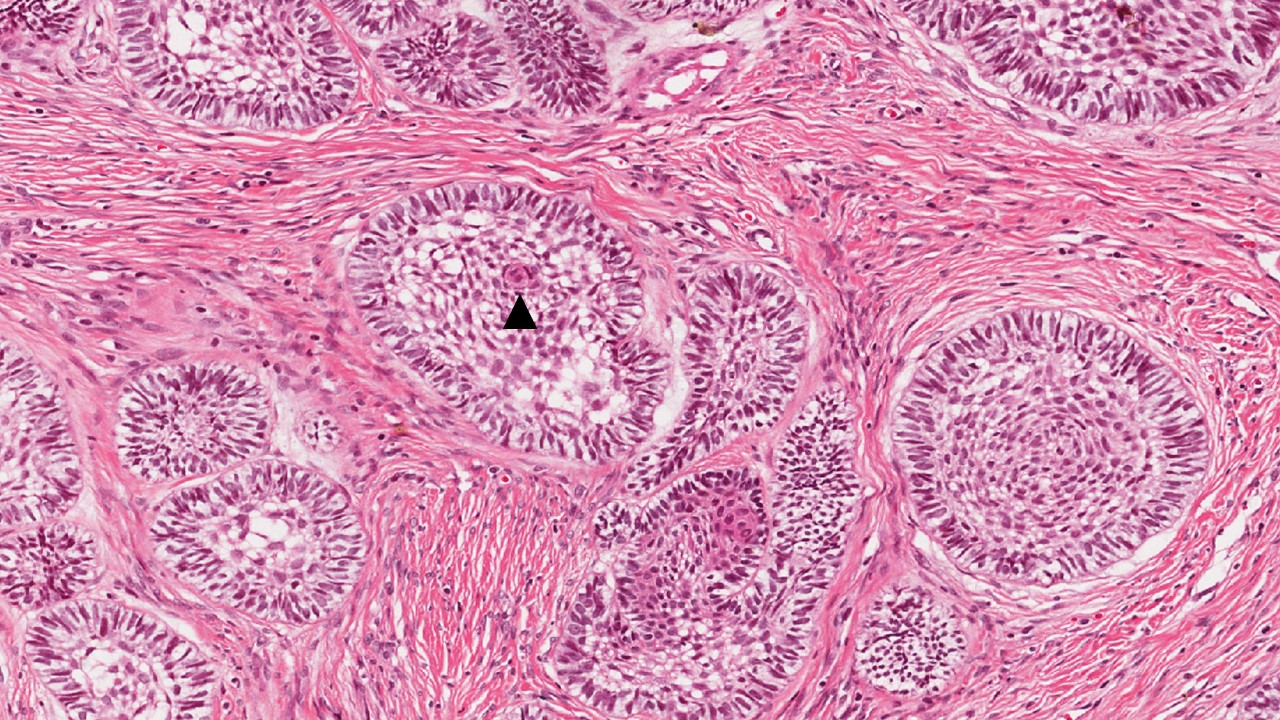

Descrição microscópica:

Ilhas de epitélio odontogênico entremeadas por estroma de tecido conjuntivo denso. As ilhas epiteliais consistem em uma região central de células arranjadas frouxamente, lembrando o retículo estrelado de um órgão do esmalte. Na periferia das ilhas nota-se camada de células colunares altas, semelhantes à pré-ameloblastos com núcleo hipercromático e polaridade invertida. Algumas ilhas apresentam metaplasia escamosa e/ou degeneração cística.

Dados importantes para o diagnóstico:

- Ilhas de tecido epitelial odontogênico (área demarcada);

- Células na periferia das ilhas, alongadas (em paliçadas) lembrando pré-ameloblastos (setas pretas);

- Células internas frouxamente arranjadas lembrando retículo estrelado (estrela);

- Tecido conjuntivo denso com aspecto de normalidade (asterisco);

- Metaplasia escamosa (triangulo);

- Degeneração cística (seta branca).